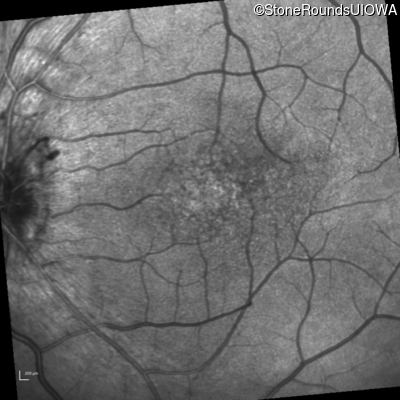

Visit at age: 16 years

Infrared Fundus Photograph - Right - 20/30 -2

Exemplar